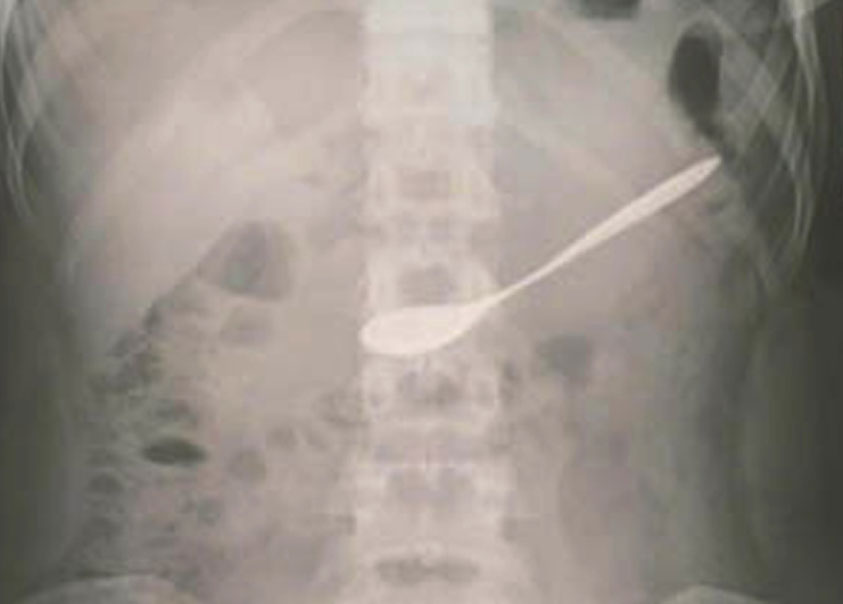

Gắp thành công chiếc thìa ra khỏi dạ dày bệnh nhân

Trước đó, khoảng 12 giờ ngày 9.6, bệnh nhân Lê Thị N.A., SN 1997, trú tại huyện Hưng Nguyên, Nghệ An cùng bạn bè đi uống cà phê, trong lúc uống cô ngậm chiếc thìa, không may bị bạn thúc vào tay làm cô nuốt luôn chiếc thìa vào bụng.Bệnh nhân được người nhà và bạn bè đưa đến bệnh viện.Tiến hành hội chẩn, các bác sĩ quyết định thực hiện phương pháp nội soi dạ dày gắp dị vật qua ống mềm cho bệnh nhân và đã gắp thành công chiếc thìa ra khỏi dạ dày, sức khỏe bệnh nhân hoàn toàn bình thường và được xuất viện ngay sau đó.Theo chia sẻ của bác sĩ, rất may là chiếc thìa trơn, không có các cạnh sắc và đi vào dạ dày theo chiều dọc nên không gây tổn thương cho đường tiêu hóa.

Trước đây, bệnh viện đã tiến hành nội soi gắp dị vật cho rất nhiều bệnh nhân, tuy nhiên đây là trường hợp hiếm gặp khi dị vật có kích thước lớn như chiếc thìa.